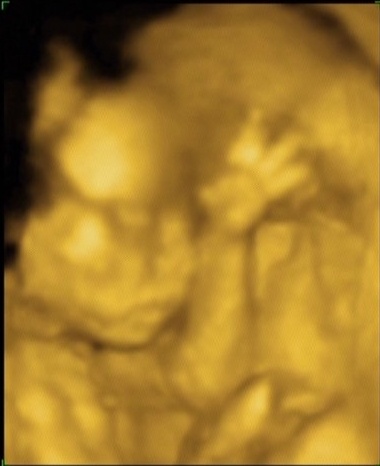

Szép kálvária volt a doki, de örülök, hogy minden rendben! Nagyon szépek a képek, tök formás már ilyen idősen. Az én kiscsajomnak ugyanebben a korban sokkal vékonyabb arca volt, de akkor ezek szt rám ütött, mert nekem is vékony az arcom.